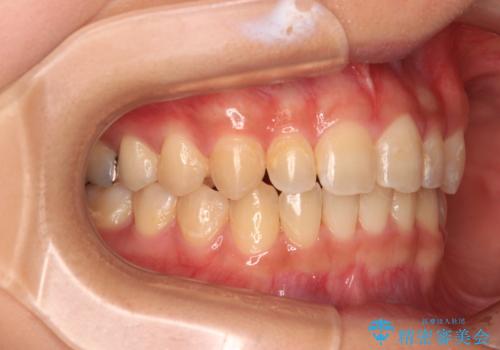

- 前歯のデコボコと深い咬み合わせを改善したいとのことで来院された患者様です。

奥歯の咬み合わせは上顎に対して下顎が後方位にあり、上顎前歯で下顎前歯が隠れるような典型的な過蓋咬合です。

補助装置を用いて上顎大臼歯を後方に移動させながら、ワイヤー装置で歯列を整えて深い咬み合わせを挙上することとしました。

下顎の装置が頻繁に脱落し、治療は難航しましたが、当初予定の2年間で無事に治療を終えることができました。